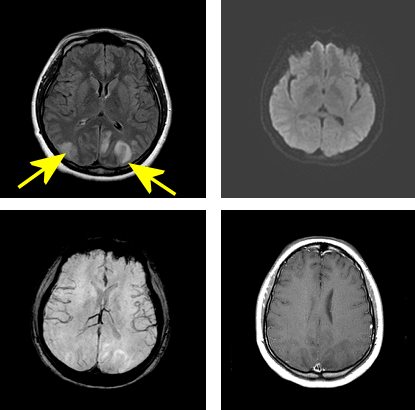

Diagnosis: Posterior Reversible Leukoencephalopathy syndrome (PRES)

Figure 1: Top left. Axial FLAIR demonstrates bilaterally symmetric subcortical T2/FLAIR signal abnormality with a posterior predominance, yellow arrow. There is no restricted diffusion to suggest infarct (top right), no increased susceptibility to suggest hemorrhage (bottom left) and no contrast enhancement (bottom right).